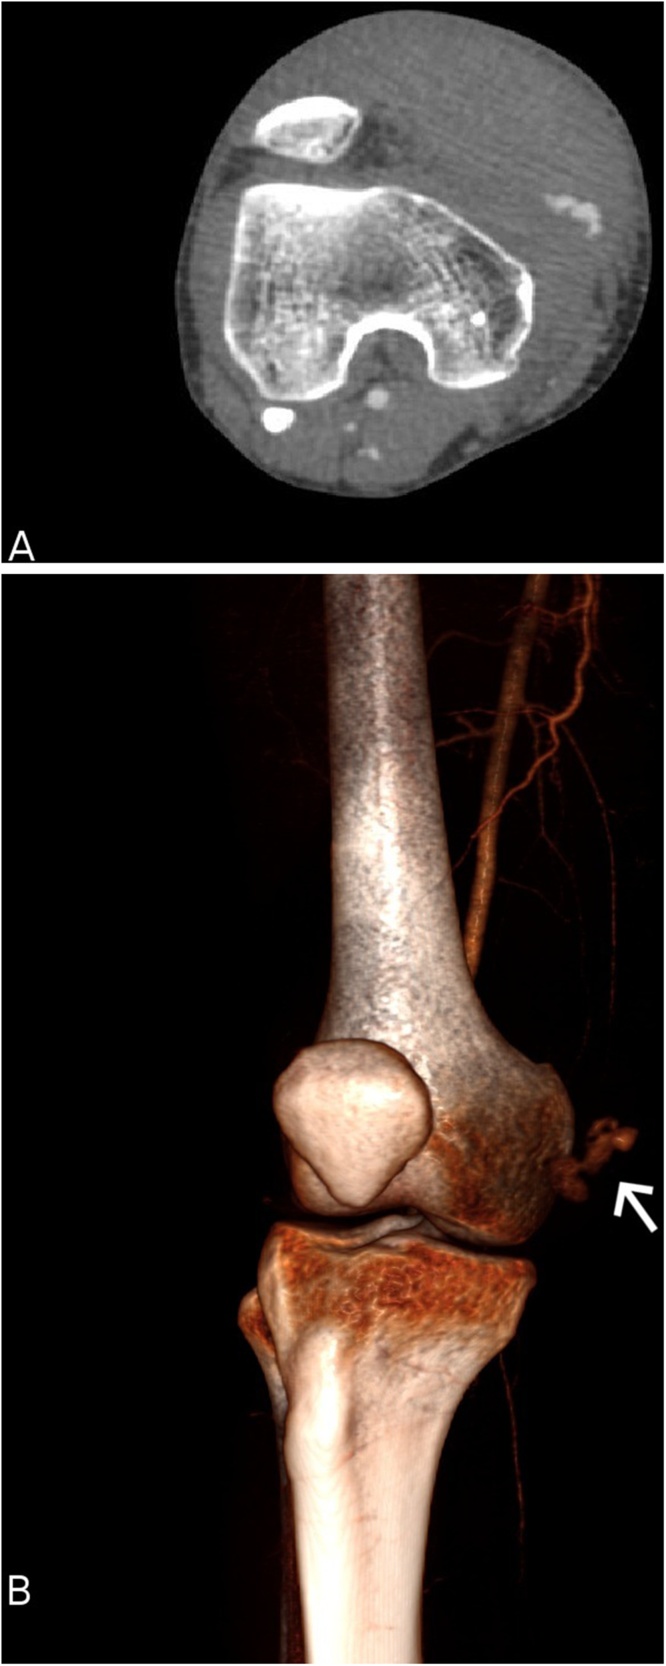

Fig. 1.

Knee contrast-enhanced computed tomography (CT). Axial view (A) showing a large haematoma in the medial side of the knee. 3D CT reconstruction (B) revealingactive bleeding (arrow) from the descending genicular artery (DGA).